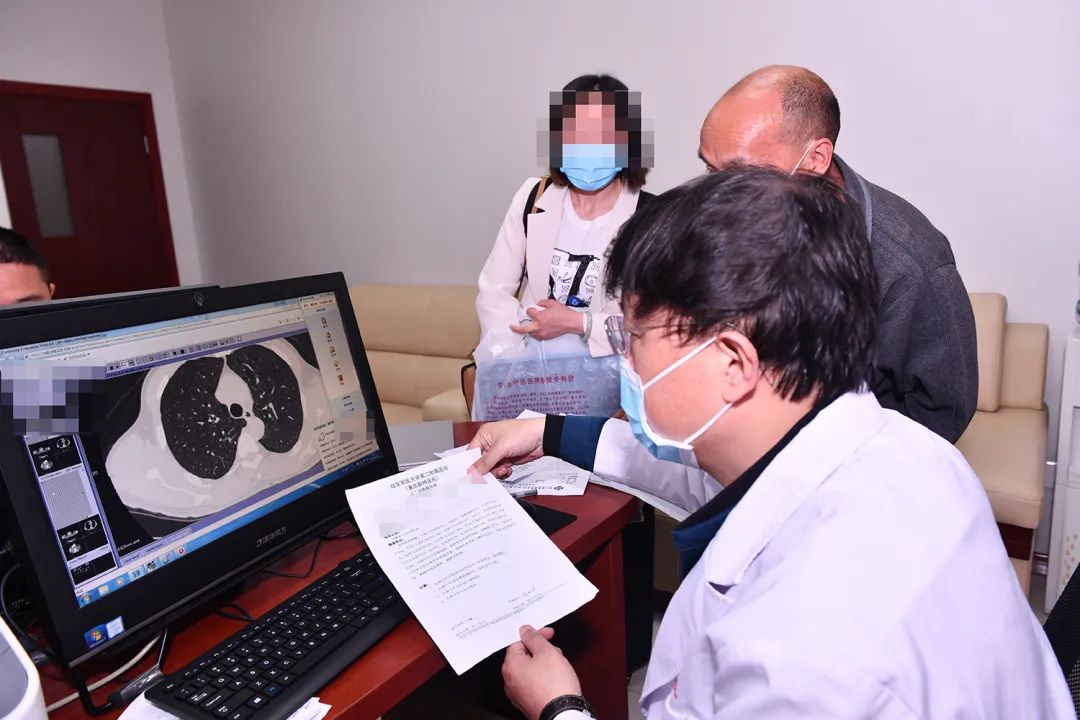

罗清泉,男,主任医师,上海市肺部肿瘤临床医学中心副主任,硕士生导师。擅长肺、食管、纵隔、气管等胸外科疾病诊断和手术治疗。从事胸外科工作近20年,在肺癌、纵隔肿瘤、食管、气管等胸外科手术的临床和基础方面积累了丰富的经验,主要擅长胸部疾病的外科治疗,包括肺、食管、气管、纵隔等各类胸部疾病;共参加手术5000余例,主刀3000余例,包括许多重症和凝难杂症。